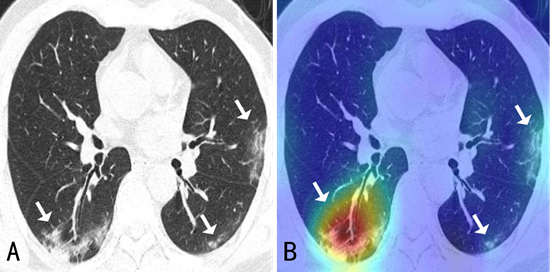

CT影像和算法模型检测后的可视化结果(演示区域存在病灶)

“现阶段医生需要在大量影像数据中快速诊断出新冠肺炎的病例,此外还需要诊断出病灶分布的位置、大小等来评估严重程度。”薛向阳介绍,针对临床的现实需求,团队将设计目标定位于“肺炎分类鉴别”和“关键病灶检测”两大功能,前者是为区别健康状态、新冠肺炎、其他病毒性肺炎、细菌性肺炎,后者则为找到并分隔出磨玻璃影等病灶区域。